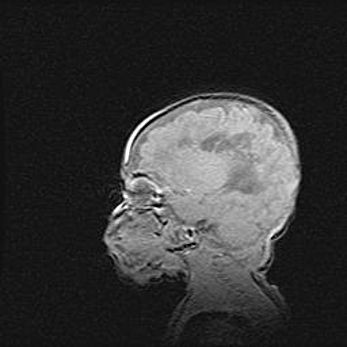

Лейкомаляция с кистозно-глиозной дегенерацией головного мозга.

Возраст: 2 месяца 25 дней

Вес: 6400 г

Окружность головы: 40 см

Срок гестации: 41 неделя

Лейкомаляцию относят к ишемически-гипоксическим повреждениям головного мозга, диагностируемым у новорожденных. При лейкомаляции в головном мозге обнаруживают очаги некроза, возникшие после тяжелой гипоксии и нарушения кровотока. В процессе морфогенеза очаги проходят три стадии: 1) развития некроза, 2) резорбции и 3) формирования глиозного рубца или кисты. Перивентрикулярная лейкомаляция (ПЛ) встречается примерно в 12% случаев среди новорожденных, обычно – у недоношенных детей, причем, частота ее зависит от массы, с которой младенец появился на свет. Наибольшее число малышей страдает лейкомаляцией, если масса при рождении 1500-2500 г.